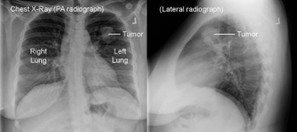

Ακτινογραφία Θώρακος

Η ακτινογραφία θώρακος αποτυπώνει εικόνες όλων των δομών του θώρακα (οστών, πνευμόνων, καρδιάς, αγγείων, σπονδυλικής στήλης κλπ).

Η ακτινογραφία θώρακος μπορεί να χρησιμοποιηθεί ως ένα πρώτο βήμα για τη διάγνωση του καρκίνου του πνεύμονα, ειδικά σε συνδυασμό με σύγχρονες τεχνολογίες όπως η τεχνητή νοημοσύνη. Σε περιπτώσεις όπου υπάρχει υποψία ύπαρξης όγκου ή άλλης βλάβης, η περαιτέρω διερεύνηση με πιο εξειδικευμένες απεικονιστικές μεθόδους, όπως η αξονική τομογραφία, μπορεί να είναι απαραίτητη. Η προσέγγιση αυτή επιτρέπει τη βελτίωση της διαγνωστικής ακρίβειας, ενώ ταυτόχρονα καθιστά τη διαδικασία πιο προσβάσιμη και οικονομικά αποδοτική για τους ασθενείς.

Η ακτινογραφία θώρακος χρησιμοποιείται για την αναγνώριση και την αξιολόγηση διαφόρων πνευμονικών παθήσεων, συμπεριλαμβανομένου και του καρκίνου του πνεύμονα.

Ωστόσο, ορισμένες φορές λόγω της επικάλυψης μικρών βλαβών από άλλες ανατομικές περιοχές και της χαμηλότερης ακρίβειας, η ακτινογραφία θώρακος έχει κάποιους περιορισμούς στην αναγνώριση μικρών ή πρώιμων βλαβών που εμφανίζονται στα αρχικά στάδια της νόσου. Ωστόσο, η έρευνα πρόκειται να βελτιώσει την διακριτική της ικανότητα μέσω ενσωμάτωσης τεχνητής νοημοσύνης.